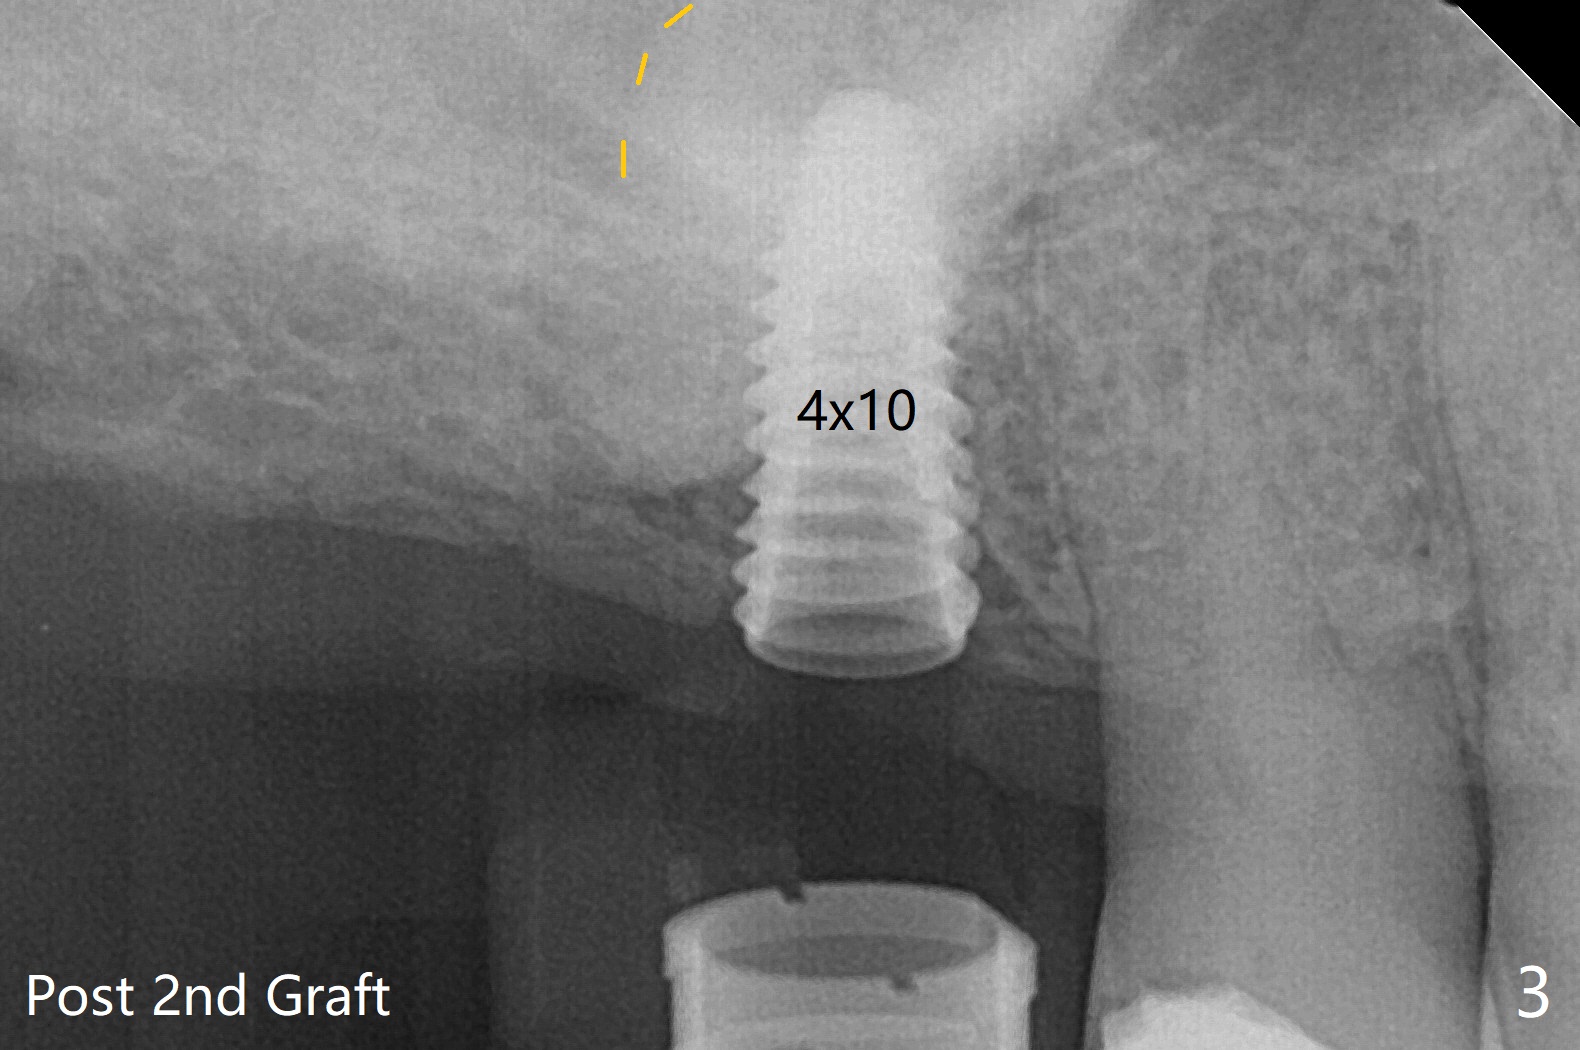

在导板协助下,顺利完成右上6钻洞,用圆钻穿过上颌窦底板,然后使用粘性骨粉(之前半张PRF膜)和4乘10毫米报废植体做第一次(图一,二),第二次(图三),第三次(图四,五)提升,退出报废植体后,拧入正式植体(4.5乘8.5毫米)。由于扭力大约10Ncm,放置愈合螺帽。植体颊侧骨壁比较低,螺帽上放置骨粉(图四,五:*),后者太多,再没有空间放置PRF膜,只好放置在骨粉表面,容易滑动,所以需要安置间隙保持器(图四,五)。在拍摄根尖片时,PRF膜丢失,只好在骨粉表面放置Teflon,然后放置牙周敷料,借助保持器固定。术后两周牙周敷料脱落,而间隙保持器仍在,下面牙龈基本愈合(图六,7)。今后使用导板做上颌窦提升,种植,最好使用导板的环形刀在牙龈上轻轻做过标记,然后用Biopsy Punch完整切除牙龈,放置于PRF上清液备用。如果植体扭力低,放置骨粉后,覆盖切除的牙龈,牙周胶水固定。